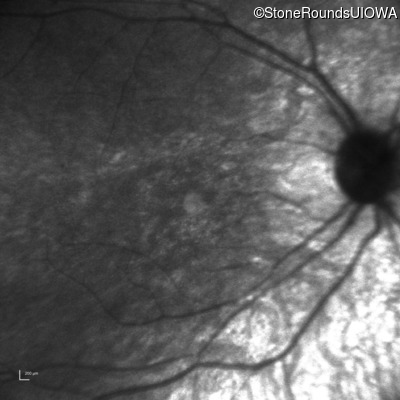

Age at visit: 8 years

OD OS

This 8 year old girl had normal vision until age 6 when she failed a school vision screening. That year, she was able to play softball well, but this year she often loses sight of the ball and is often hit by it.